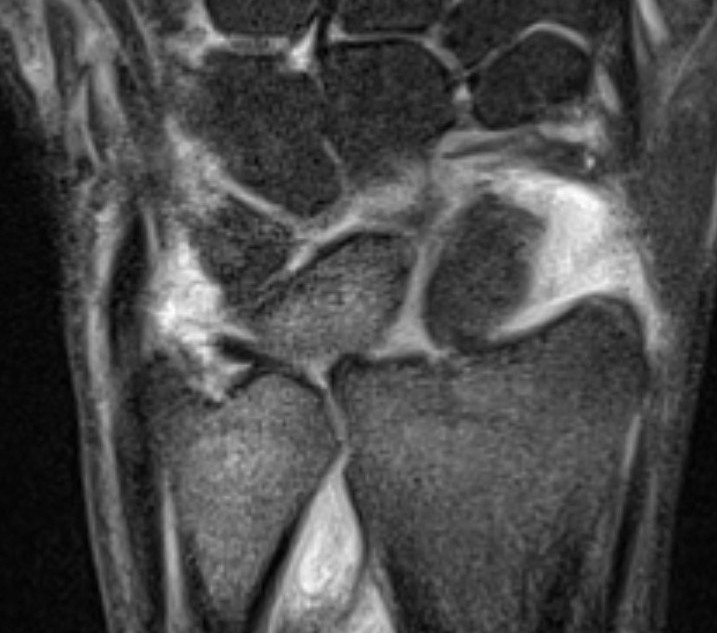

TFCC tears

Ulna sided tear